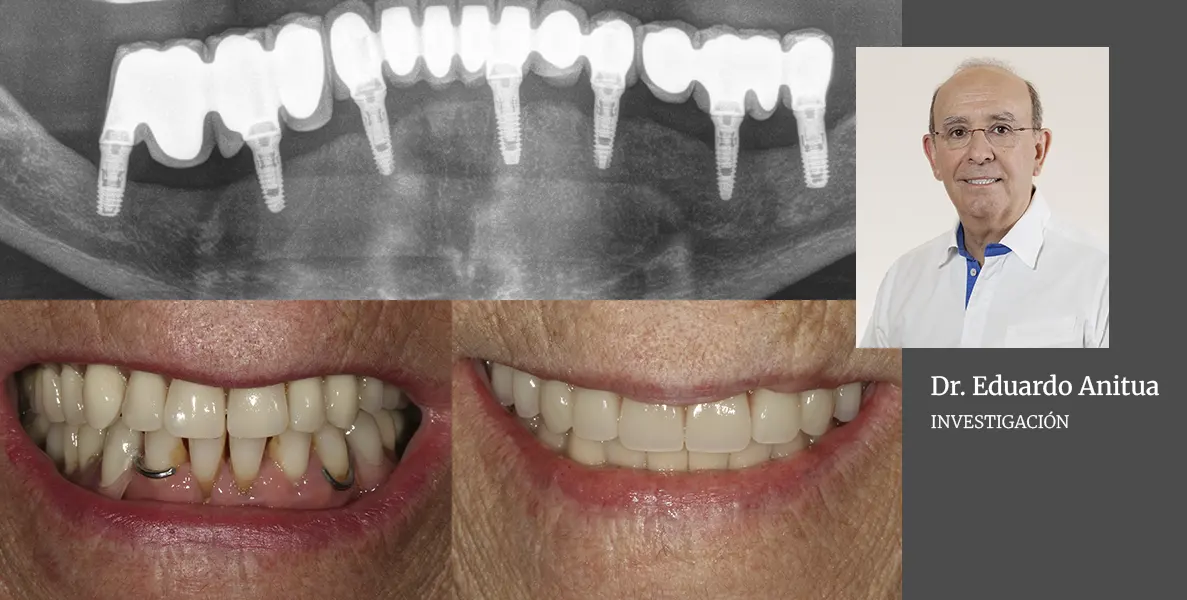

articulo indice H investigación odontología

Propuesta de nuevo ranking basado en índice H para investigación odontológica en universidades españolas